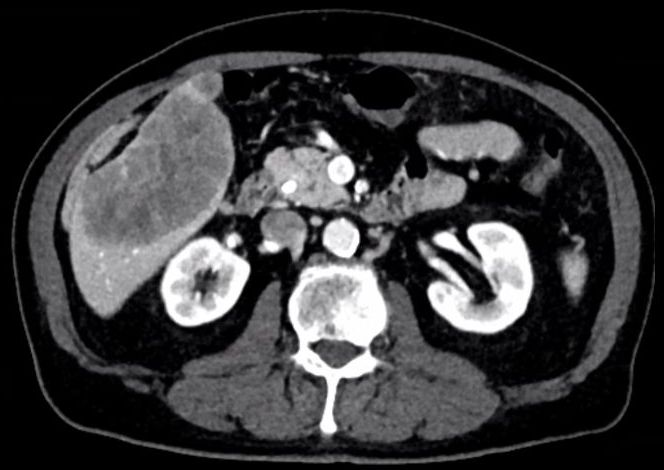

Histologie: knotige und solide Tumorinfiltrate aus rundlichen und länglichen, z. T. verzweigten Tumordrüsen mit mäßiger Zell- und Kernpolymorphie. Einreihige Epithelschichtung. Vergrößerte, z. T. übereinander gelagerte Zellkerne mit prominenten Nukleolen. Vermehrt Mitosen. Exprimieren Zytokeratin 7 und kleinherdig Zytokeratin 20. CEA und CDX 2 sind negativ. Gut differenziertes tubuläres Adenokarzinom. ![]() | |